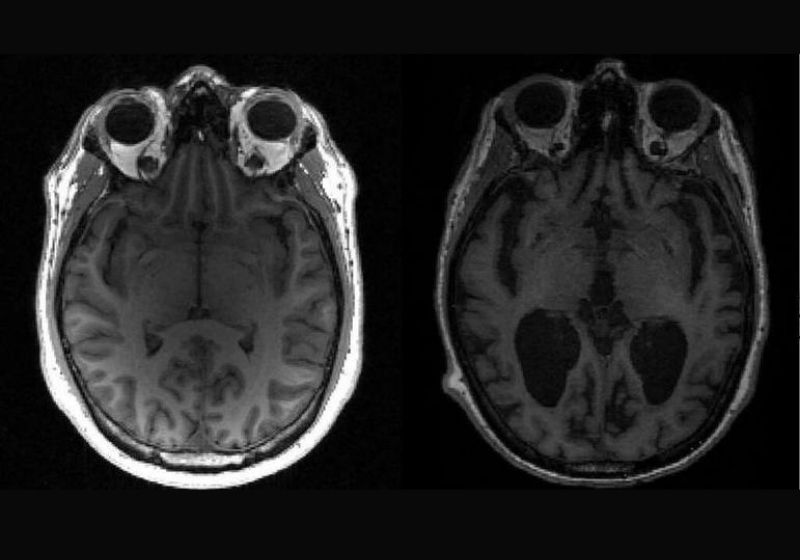

Na doença de Alzheimer, a tau e outra proteína chamada beta-amiloide se acumulam em agregados e fazem com que as células cerebrais morram e o cérebro encolha.

É esse processo que resulta em perda de memória, alterações de personalidade e dificuldade para realizar as tarefas cotidianas.